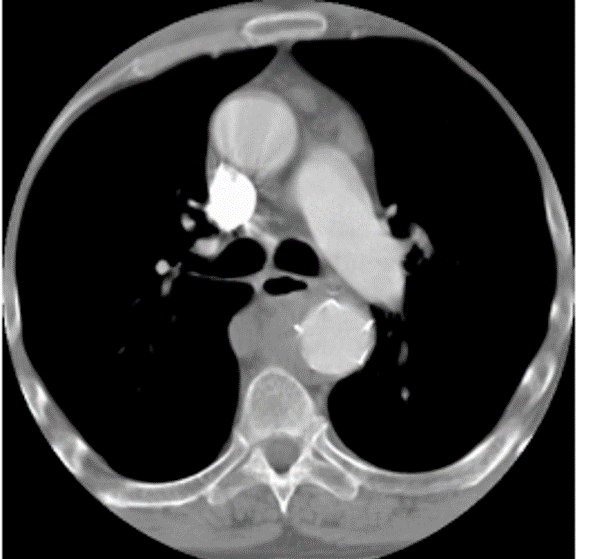

beam hardening due to contrast